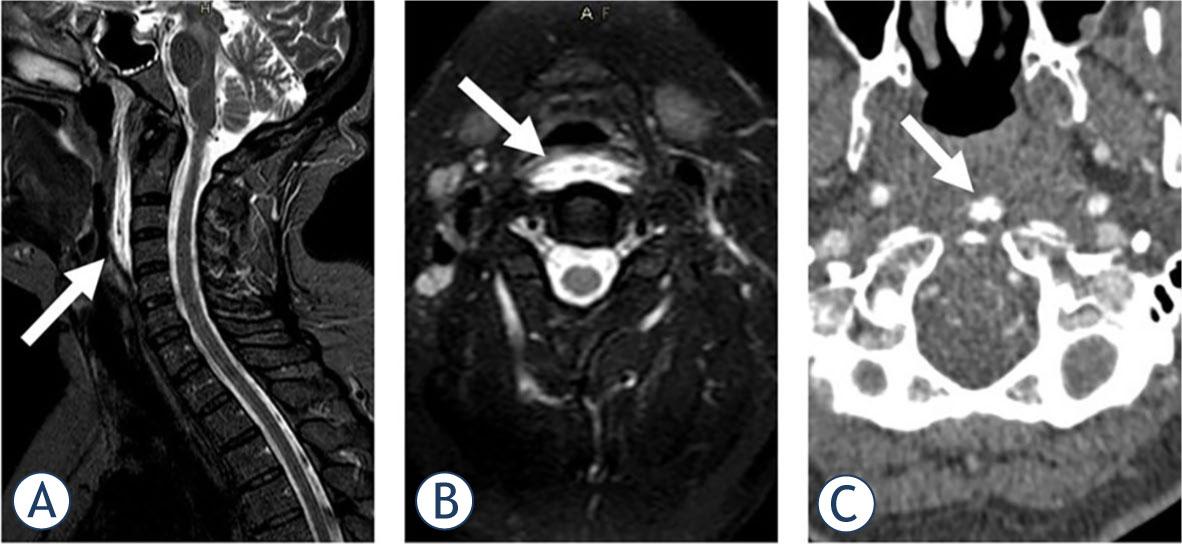

A previously healthy 40-year-old female with suspected meningitis was referred to our institution in November 2020. She was experiencing excruciating throbbing neck pain, which had developed spontaneously within 12 hours without any trauma or heavy mechanical load. She complained that swallowing was painful and that the pain increased with any attempt to move the head. A neurological exam showed severe neck stiffness with immobility in all directions as well as dysesthesia over the vertex and occipital regions. Laboratory workup revealed only mildly increased C reactive protein (CRP) of 20 mg/l (normal value < 5 mg/l) and white blood cell count (WBC) of 10.2 (normal < 10×109/l). Although the patient was afebrile, the retropharyngeal abscess was still considered in the differential diagnosis. Magnetic resonance imaging (MRI) of the neck showed fluid collection and swelling in the cranial part of the longus capitis/colli muscle on the left (Figure 1). A lumbar puncture was also performed, but the CSF was normal. She was treated in the NEU and discharged with ketoprofen 200 mg daily and a soft neck collar. The pain resolved in one month.

MRI in a 40-year-old female showed short tau inversion recovery sequence (STIR) hyperintensity in the upper part of her left Longus colli muscle, suggesting an oedema (A), with thin prevertebral effusion on sagittal images (B). After intravenous gadolinium contrast injection, a small area of enhancement was observed in the medial aspect of the muscle (C), but no peripherally enhancing collection to suggest an abscess was present. Diffusion-weighted imaging was normal, excluding the presence of pus (D).